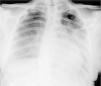

Caso clínicoAdolescente de 14 anos, sexo feminino, com antecedentes pessoais de enxaqueca hemiplégica e quisto pineal, submetida a ressonância magnética (RM) cranioencefálica de controlo. Durante a indução anestésica com propofol verificou‐se bradicardia, revertida com atropina, seguida de taquidisritmia ventricular, revertida com lidocaína e murro pré‐cordial. Nas primeiras horas de internamento evoluiu para edema pulmonar (Figura 1) associado a insuficiência respiratória global (SaFi 156, PCO2 57mmHg) e hipotensão (89/56mmHg, PAS e PAD <p5). O ecocardiograma transtorácico mostrou dilatação do ventrículo esquerdo com hipocinesia global envolvendo todos os segmentos meso‐basais, mas poupando o ápex, condicionando compromisso moderado a grave da função sistólica global do ventrículo esquerdo e fração de ejeção reduzida (<30%) (Figuras 2 e 3). O eletrocardiograma (ECG) revelou taquicardia sinusal persistente e alterações inespecíficas do segmento ST em V4 e V5 (Figura 4). Os biomarcadores cardíacos encontravam‐se elevados (CK total 217UI/L, troponina I 2,42ng/ml, pro Peptido Natriurético Cerebral [proBNP]) 8284pg/ml). Foi medicada com diuréticos e captopril, havendo necessidade de terapêutica com dopamina para otimização da função renal (máximo 2mcg/kg/min) e digoxina nas primeiras 24h. Foram realizados ecocardiogramas diários, verificando‐se melhoria clínica e imagiológica nas primeiras 48h e recuperação completa da função sistólica do ventrículo esquerdo em D4. Os valores dos biomarcadores cardíacos diminuíram ao longo dos primeiros dias (troponina I 0,69ng/ml em D2 e 0,44ng/ml em D3; proBNP 2842pg/ml em D3) com normalização em D6 dos valores de CK I total e troponina I e descida significativa do proBNP (329pg/ml). Suspendeu diuréticos em D9 e teve alta medicada com carvedilol. A RM cardíaca não mostrou alterações, nomeadamente cicatriz de miocardite ou enfarte, tendo suspendido terapêutica com carvedilol. Da investigação realizada salienta‐se função tiroideia normal e serologias virais (CMV, EBV, HSV 1, HSV 2, HSV 6, parvovírus, adenovírus, influenza A e enterovírus) negativas. Manteve acompanhamento regular em consulta de cardiologia pediátrica.